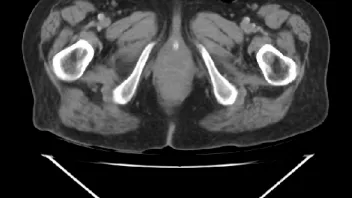

ist jemand unter Euch der sich auskennt mit CT Aufnahmen ?

Ich habe 3 Stück angehangen, sie stammen aus einem CT der Abdomen.

Möglich das es eine Serie eines Querschnitts darstellt Bild 1 zeigt den Start,Bild 2 eines aus den mittleren Aufnahmnen und Bild 3 das letzte dieser CT Serie.

Da ganz gezielt auf ein und die gleiche Stelle gehalten wurde mit sagenhaften über 80 Einzelaufnahmen interessiert mich brennend um die Darstellung welches Organges es sich bei diesen Aufnahmen handelt und ob darauf etwas bedenkliches eingekreist wurde.